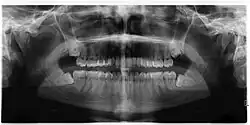

Impacted wisdom teeth is a condition where the third molars (wisdom teeth) are prevented from erupting into the mouth.[1] This can be caused by a physical barrier, such as other teeth, or when the tooth is angled away from a vertical position.[2] Completely unerupted wisdom teeth usually result in no symptoms, although they can sometimes develop cysts or neoplasms. Partially erupted wisdom teeth or wisdom teeth that are not erupted but are exposed to oral bacteria through deep periodontal pocket, can develop cavities or pericoronitis. Removal of impacted wisdom teeth is advised for the future prevention of or in the current presence of certain pathologies, such as caries (dental decay), periodontal disease or cysts. Prophylactic (preventative) extraction of wisdom teeth is preferred to be done at a younger age (middle to late teenage years) to take advantage of incomplete root development, which is associated with an easier surgical procedure and less probability of complications.[3]

Impacted wisdom teeth are classified by their direction of impaction, their depth compared to the biting surface of adjacent teeth and the amount of the tooth's crown that extends through gum tissue or bone. Impacted wisdom teeth can also be classified by the presence or absence of symptoms and disease. Screening for the presence of wisdom teeth often begins in late adolescence when a partially developed tooth may become impacted. Screening commonly includes a clinical examination as well as x-rays such as panoramic radiographs.